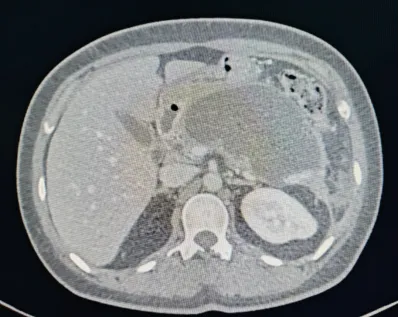

治疗前胰腺假性囊肿CT影像

入院后超声胃镜检查提示:张女士胰腺体尾部存在一大小约8.7cm的囊性灶,诊断为胰腺假性囊肿。

胰腺假性囊肿是AP最常见的并发症之一,并非真正的肿瘤,而是胰腺受损后,胰液、血液、坏死组织等积聚在胰腺周围,被周围组织包裹形成的局限性、非上皮性的囊性病变。